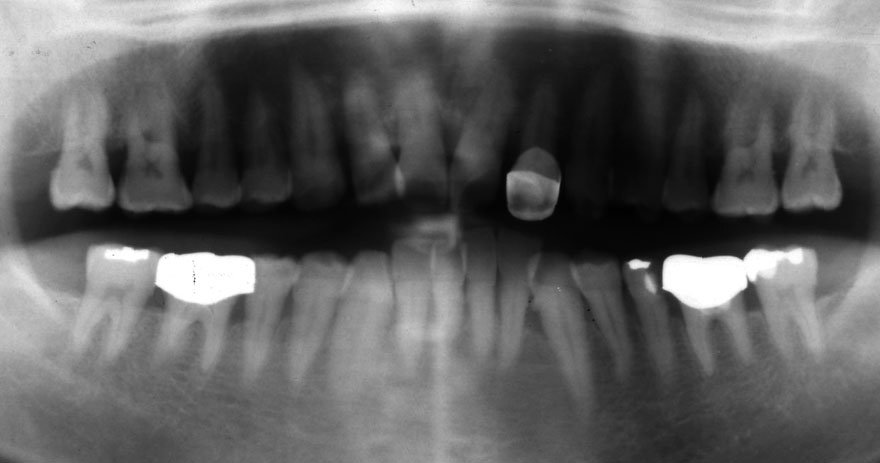

初診時 50歳 女性

河田歯科医院

22年後 72歳